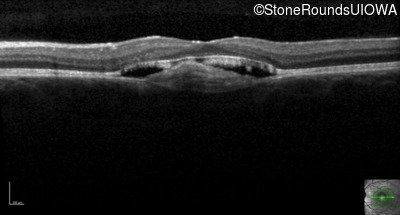

Visit at age: 18 years

Optical Coherence Tomography - Right - 20/40 -1 sc

Exemplar / OCT Stack

OCT Stack